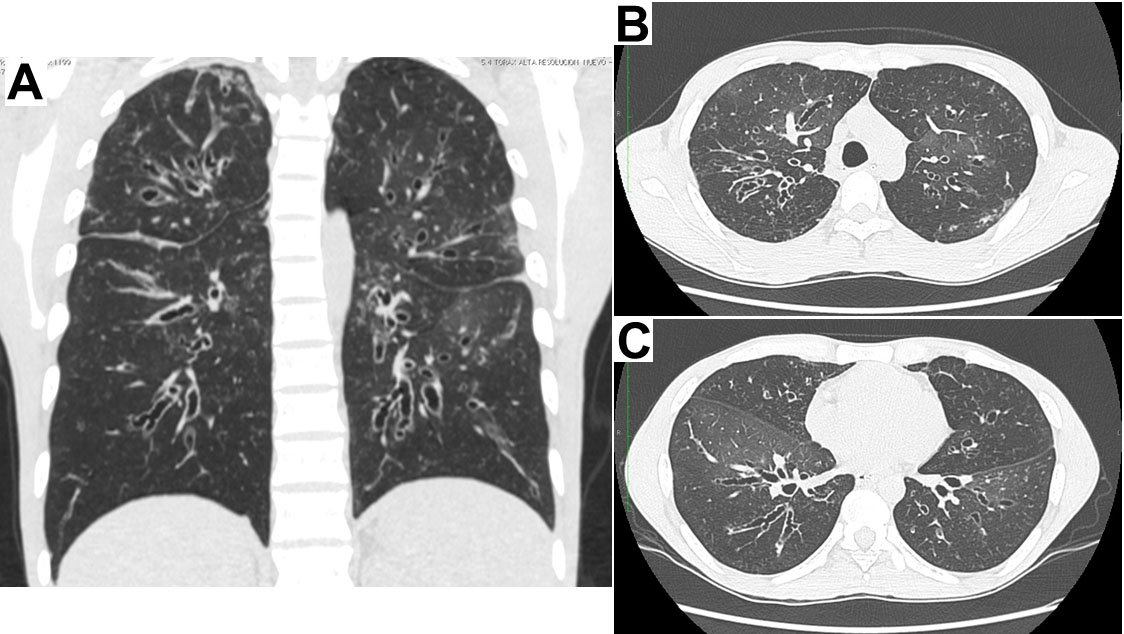

The patient is native to, and came from Cali (Valle province, in Colombia). As relevant background, he refers pneumonia, sinusitis and recurrent otitis since he was aged 18 years, with countless episodes (6 to 10 per year) requiring long courses of oral or intravenous antibiotics and multiple hospitalizations. Since 2002 cylindrical and cystic bronchiectasis had been documented in all four quadrants (Fig. 1A), equally documented in the cross sections at the level of the aortic arch and the left ventricle (Fig. 1B y1C).

Figure 1.

High resolution chest scans which show widespread bronchiectasis in the four quadrants (A); and in the cross sections at the level of the aortic arch (B), and the left ventricle (C).